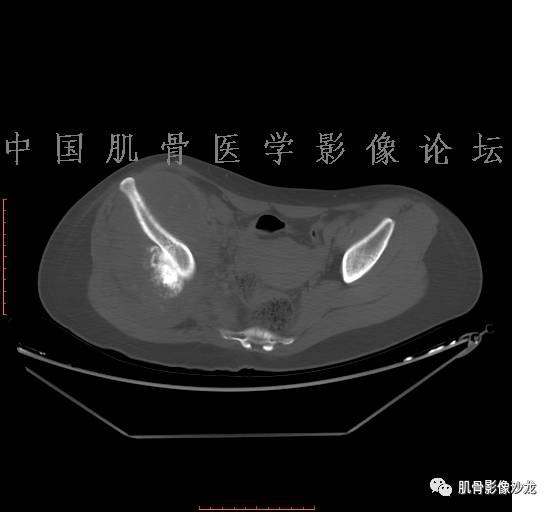

患者2月前无明显诱因下感右腿疼痛、麻木,疼痛呈持续性,发作时无法行走,休息后可缓解。当时无明显肿块,患者遂至当地医院就诊,查X片见右髂骨骨质破坏。6周前患者自觉右髋部渐大肿块,初肿块较小,后肿块逐渐增大,现肿块约12*10cm大小,有压痛。患者遂至我院就诊,查MRI:右髂骨异常信号,伴软组织肿块。ECT、肺CT未见转移。现患者为求进一步治疗,门诊拟“右髂骨肿块 ”收治入院。 患者发病来,神清,精神可,胃纳夜眠可,二便无殊,体重无明显变化。

1、软骨肉瘤可以有膨胀性骨质破坏(病例3,4),可以有溶骨性骨质破坏(病例2),局部皮质因为破坏变薄,中断 ;

2、软骨基质T2WI高信号,软骨小叶分叶状,也就会出现高老师提到的骨内膜扇贝形压迹。一般认为骨内膜扇贝形压迹超过骨皮质厚度的2/3是软骨肉瘤在长管状骨的特征性表现。如上图。3、软组织肿块或肿胀;

4、 钙化,环形,弓形,边缘模糊 ;

5、增强后进行性延迟,不均匀分割状强化, 会强化的纤维间隔,软骨小叶不会强化,关于老师们说到的钙化,软骨肉瘤不一定会有钙化 。

2、软骨肉瘤的发病部位排名:最好发部位为髂骨,其次股骨、肱骨和脊柱。